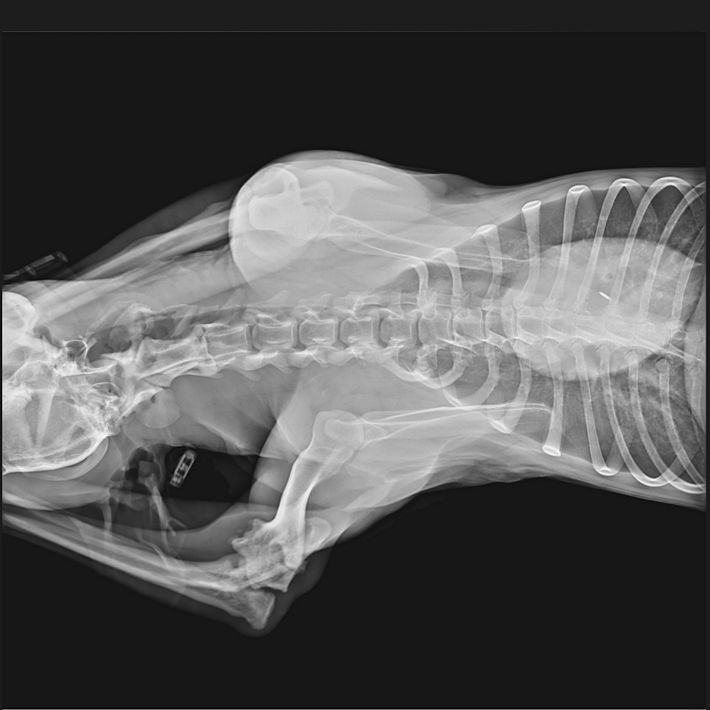

Miro wurde mit einer Fraktur des Ellenbogens aus der Tötung gerettet. Leider war die Verletzung schon zu alt um zu operieren. Miro hat sich mittlerweile damit arrangiert und belastet das Bein.

Handicap